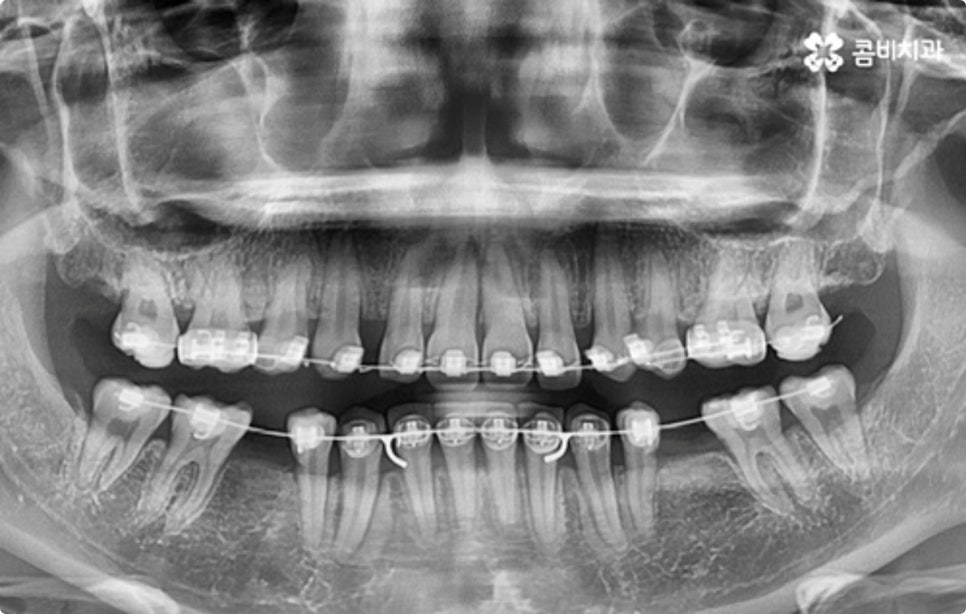

클리피씨 교정도 치아 색상의 세라믹 재질을 사용하기 때문에 심미성이 높은 편이지만 만약에 장치가 아예 겉으로 드러나지 않았으면 좋겠다고 생각하신다면 브라켓을 치아 안쪽에 부착하는 설측교정을 이용할 수 있는데요. 하지만 설측교정은 혀와 맞닿는 부분의 이물감, 통증, 발음상 문제 등을 일으킬 수 있기 때문에 잘 보이는 윗니는 설측으로, 잘 드러나지 않는 아랫니는 보통 교정과 같이 순측 (입술쪽) 으로 진행하는 콤비교정을 통해 이를 보완할 수 있어요. 사진에서 살펴보실 수 있는 케이스 역시 이렇게 콤비로 진행한 직장인치아교정 과정으로 시간이 지날수록 점차 치열이 가지런해지고 교합이 올바르게 개선되는 것을 확인해 보실 수 있습니다.